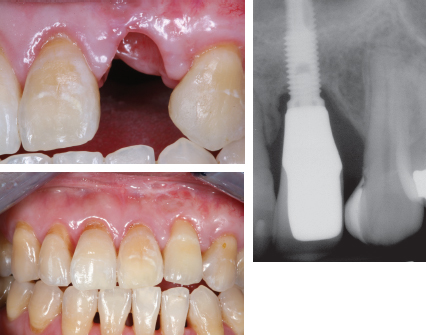

66 ○ Prosthodontic treatment planning should begin as early as possible within a cleft team setting. ○ A patient with a cleft often has significant dental issues that require intensive treatment. ○ The decision to move a canine into the position of a missing lateral incisor is as much a prosthodontic decision as an orthodontic one. ○ Long-term consequences of early treatment decisions should be considered before embarking on a particular dental treatment plan option. ○ Osseointegrated implants provide a high degree of success in replacing missing lateral incisors in properly selected patients. ○ Bone grafting is often required before implant placement for patients with clefts. ○ Many adult patients with clefts still require fabrication of a cleft speech bulb prosthesis. ○ Digital technology may greatly enhance and simplify prosthodontic care for the patient with a cleft. ○ The prosthodontist is an integral member of the cleft treatment team. Restorative dentistry or prosthodontic care for a patient with a cleft palate is often not considered until the patient has reached adulthood or until all the surgical and orthodontic care has been completed. At this point, the patient is referred to the prosthodontist to replace any teeth that are missing or are in need of restorations. Little consideration may have been given to the prosthetic or restorative treatment planning required to provide the optimum overall functional and aesthetic outcome for the patient. The patient with a cleft is best served by having a prosthodontist or restorative dentist become involved as early as possible in the treatment planning process. With the generally accepted principle that the team approach to management of patient with clefts provides the best results, the prosthodontist should become involved in treatment planning at the onset of cleft care, even as early as in infancy. The prosthodontist working with the surgeon, orthodontist, pediatric dentist, and other members of the cleft palate team at the onset of treatment is the most effective model of care. The prosthodontist must not be considered the treatment provider of last resort, to simply manage the unrepaired cleft palate or the failed pharyngeal flap or to merely replace missing teeth once all other phases of care have been completed.1 Several dental conditions are unique to patients with cleft palate. The most common finding in patients with unilateral clefts is the lack of the maxillary lateral incisor on the affected side. Duplication of the lateral incisor is not uncommon, however. Similarly, in patients with bilateral clefts, a second lateral incisor may be present on one or both sides of the maxillary dental arch, located on the premaxillary segment or on the lateral alveolar segments. This duplication of dental units often poses aesthetic challenges in the development of a natural appearance in the patient’s smile. Teeth adjacent to the cleft are often hypoplastic and dysmorphic in form. Prosthetic intervention may be required to provide balance and symmetry in the development of an aesthetic, as well as functional, final tooth arrangement. These teeth may be either larger or smaller than the tooth would normally be in an individual without a cleft. Consideration should be given to the selective extraction of teeth that will not enhance the long-term functional or aesthetic outcome. Therefore the orthodontist and prosthodontist must work closely together in establishing a symmetrical and balanced tooth arrangement while orthodontics are underway, rather than waiting for the “final” tooth position determined solely by the orthodontist. The dysmorphic shape and malposed position of teeth, combined with the increased tendency for mouth breathing, greatly increases the potential for dental caries in this patient population.2 The introduction of fixed or removable orthodontic appliances (or both) increases the potential for plaque accumulation and makes oral hygiene measures more challenging. Patients with clefts have a higher incidence of dental caries. These patients in particular should be thoroughly instructed on the proper methods of daily oral hygiene. Professional dental prophylaxis and examinations should be increased from the usual regimen of twice a year to a minimum of three times per year during the childhood and adolescent years, and perhaps even more frequently while they have fixed orthodontic appliances in place. Early prosthodontic interventions, such as placement of a fixed dental prosthesis to restore badly decayed teeth or to replace missing teeth, must take into consideration the presence of enlarged pulp chambers in the younger patient, thereby making either a carious or mechanical pulpal exposure more likely. Patients and their parents should be advised of the increased risk potential for the need for endodontic therapy for teeth that require extensive restorations. Every attempt should be made to keep tooth preparations for composite restorations, veneers, or crowns as conservative as possible in young patients. An adequate amount of tooth structure should be reduced to provide for physiologic tooth forms in the final restorations. These restorations should not increase the amount of plaque retention or compromise gingival health. In addition to the unique dental conditions that exist in patients with clefts, other important oral factors must be taken into consideration when providing prosthodontic care. A meticulous examination of the hard and soft tissues of the oral cavity, with particular attention paid to the possible presence of small or pinpoint sized fistulae (Fig. 66-1), is necessary. Dental impression material may be trapped in an unrecognized fistula or be pushed into the nasal cavity. The removal of this material may be difficult or impossible without nasal exploration. The presence of an unseen fistula may be discovered by pinching closed the patient’s nostrils and directing the patient to attempt to blow air out through the nose in a Valsalva maneuver. A high-pitched “hissing” sound may be heard or bubbling of mucous or saliva may be seen if a fistula is present. The presence of postoperative palatal scarring tends to produce posterior arch width collapse and the recurrence of a posterior crossbite if retainers are not fabricated and used regularly by the patient who has completed prosthodontic care to replace missing anterior teeth. Although a fixed dental prosthesis may serve to maintain tooth position in the anterior maxilla, unless the prosthesis is large enough and encompasses enough teeth to extend to the maxillary molars, orthodontic relapse, arch-width collapse, and redevelopment of a crossbite are likely. Fig. 66-1 Oronasal fistula at the junction of the primary and secondary palate. At cleft centers that use presurgical infant orthopedics (PSIO), such as nasoalveolar molding (NAM), the management of early infant oral and nasal molding may be undertaken by the orthodontist, prosthodontist, or pediatric dentist on the team, if the practitioner has been trained in the technique.3 The early use of PSIO appliances was initially advocated by a prosthodontist.4 In helping to manage the infant undergoing presurgical orthopedic care, the prosthodontist can become familiar with the development of the patient’s oral structures from the earliest onset of care. Children who have had a successful repair of their cleft have unique factors that should be taken into account as they grow and progress through orthodontic care and eventually into prosthodontic care. After a successful repair of the alveolar cleft, with or without a gingivoperiosteoplasty (GPP), the decision must be made before the eruption of the adult canines as to whether autogenous alveolar bone graft surgery is indicated. This determination is often made at many cleft centers by the orthodontist or surgeon alone, as is the decision to move the adult canine into the position of the missing lateral incisor. These decisions are ideally made in the setting of the cleft team, including the input of the prosthodontist who will ultimately be responsible for restoring, both functionally as well as aesthetically, the teeth in that area. This requires early collaboration between the prosthodontist and the orthodontist to determine the treatment option best suiting each particular child as they progress through their dentofacial development. A variety of orthodontic-prosthodontic pathways may be pursued. At the Institute of Reconstructive Plastic Surgery at New York University Medical Center, the orthodontic-prosthodontic evaluation usually begins at approximately 8 years old. The determination regarding what is needed to establish a solid and stable posterior occlusion is made while developing a maxillary dental midline that is as closely coincidental with the facial midline as is possible. Consideration will then be given to establishing an intact maxillary alveolus (if this has not already been accomplished through an early GPP after NAM therapy). The positions of the remaining teeth, relative to the available space, are then worked out using a series of diagnostic wax mockups as the child ages and until early adulthood. Often, the decision of whether a missing lateral incisor will best be restored with a transported canine or an osseointegrated implant is not made until the age of 16 years (Fig. 66-2).